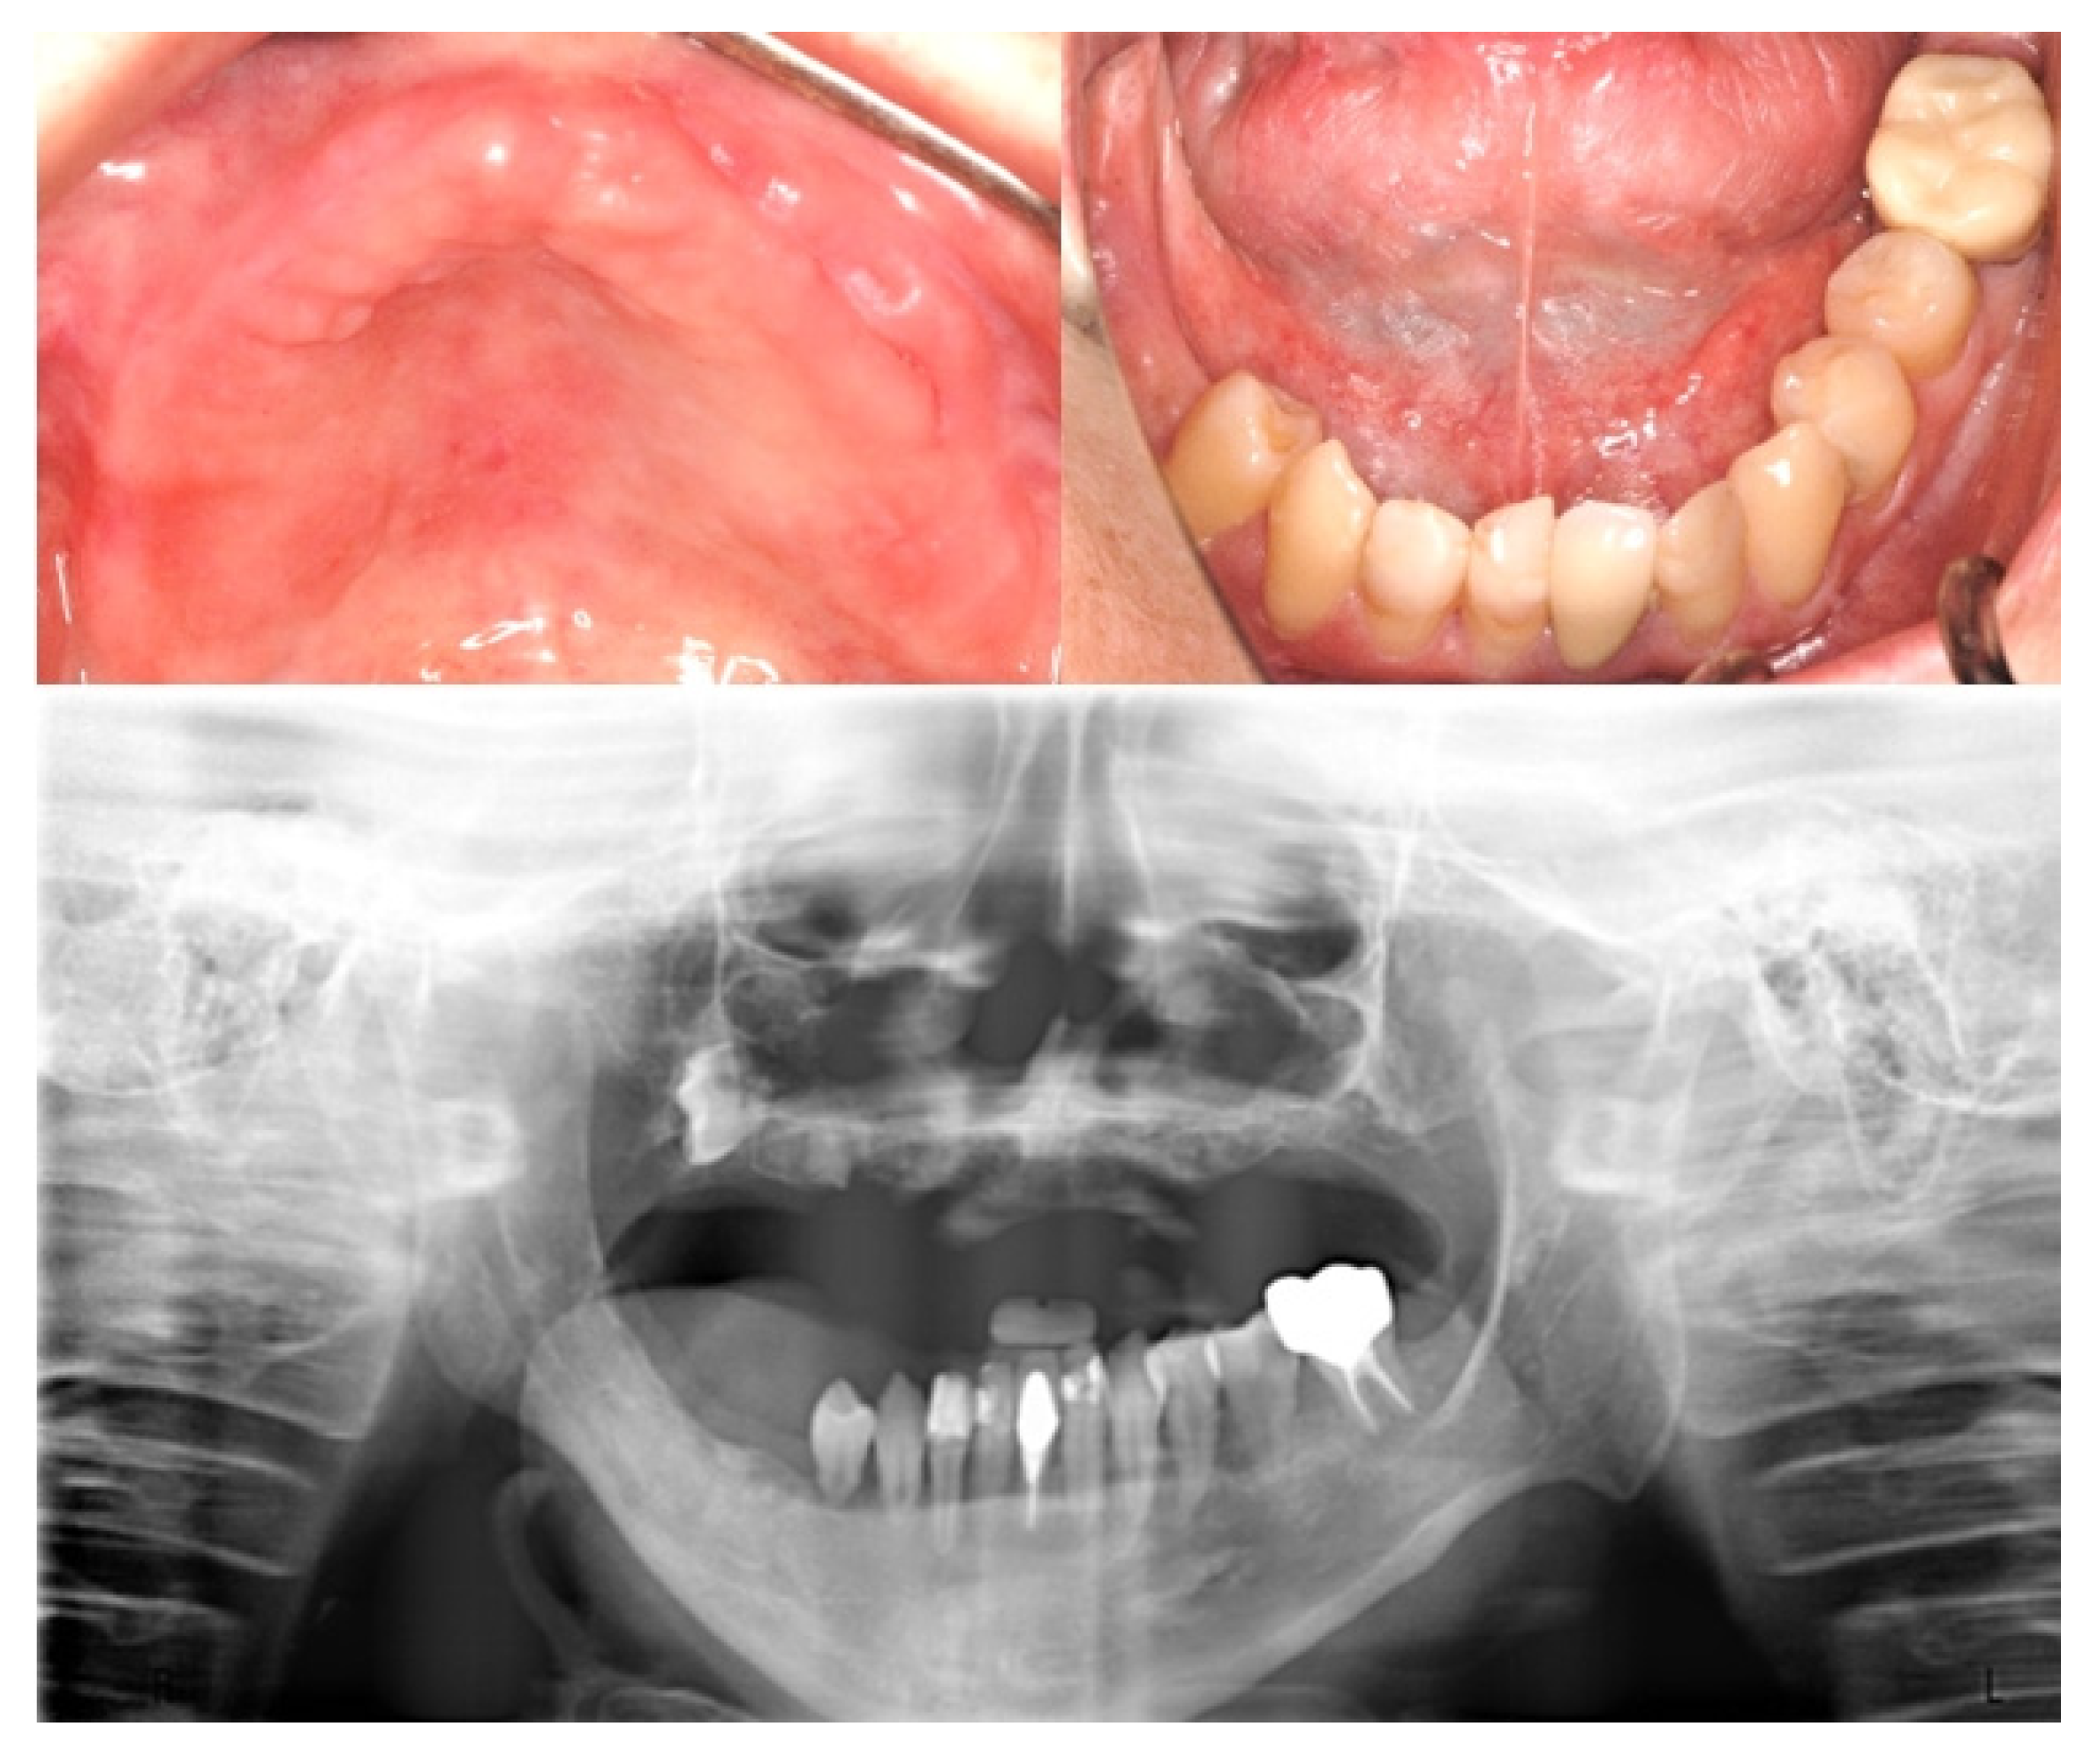

2. Case Report